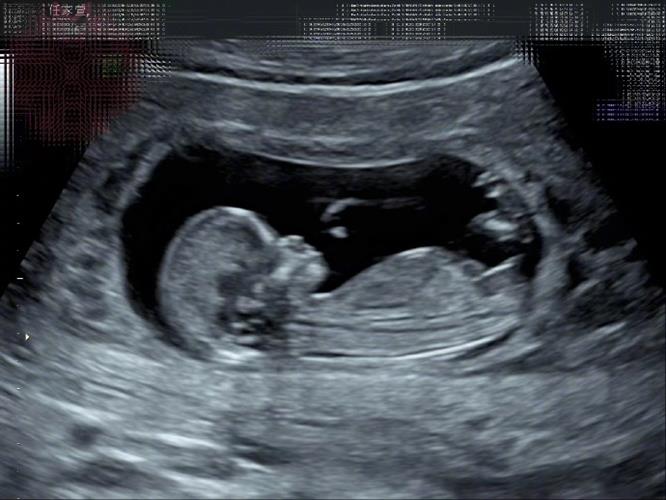

3月13日,台湾艺人、S.H.E组合成员任家萱Selina在微博发文:“真心感谢,满心喜悦,跟大家分享一个好消息。我~怀~孕~了!肚子里的宝贝,我取名叫‘小腰果’!为什么呢?欢迎收听我的节目‘迎任而解’!(哈哈哈!不忘宣传一下)加滑说:‘好可爱的小名喔,喜欢。’甄说:‘小腰果很中性,可男可女,可甜可咸,可以带皮也可以去皮,甚至顽皮。’我说:‘腰果啊~弯弯的,似微笑的眼睛。上扬的,似笑开的嘴角!妈妈希望腰果是个快乐的小孩。”

Selina宣布怀孕的微博配图。

据台媒,她今年3月13日在微博、电台宣布怀孕喜讯,目前怀孕12周。Selina透露,先前熬夜跨完年觉得身体不舒服,隔几天想说测一下,立刻出现两条线,“觉得我眼花有这么严重吗?这是怎么回事?”打给男友帮忙买其他牌子的验孕棒测试,讲到激动处还一度感动哭出来,坦言当下眼泪当场喷出来,“我要当妈妈了,真的就哭了。”